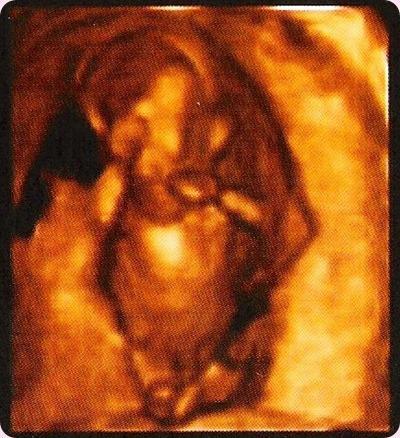

Lo primero que tengo que deciros es que: es NIÑAAAAAA!!! si si si, traigo una niña, que ilusión por favor! jajajaja no os voy a engañar, evidentemente en mi situación viniera lo que viniera ya ves… estupendo, solo pido que venga sano, pero sinceramente… me hacía mucha ilusión que fuese niña, y mira por donde, niña! estamos que no nos lo creemos, locos de contentos la verdad, sobre todo porque parece que por lo menos por ahora, la cosa va bien, el bebe está bien y yo también (algún achaque… por lo mío… pero soportable). Nos lo han dicho muy prontito, estando de 12 semanas pero bueno, espero que no se hayan equivocado jajaja asi que por fin voy a poder ponerle lacitos en el pelo, vestiditos y todos esos complementos tan monos que tienen las niñas, entro en el mundo rosa! eso si, el rey de mi casa sigue siendo mi Adri eh? que conste! jajaja os dejo una foto de mi niña (todavía estamos debatiendo nombre… ya os contare…), la eco corresponde a 12+4 semanas de gestación, y esa cosita que veis mide 69mm, a que es una pasada? parece increíble que “algo” tan chico este ya asi de formadito y sea capaz de darte tanta felicidad…